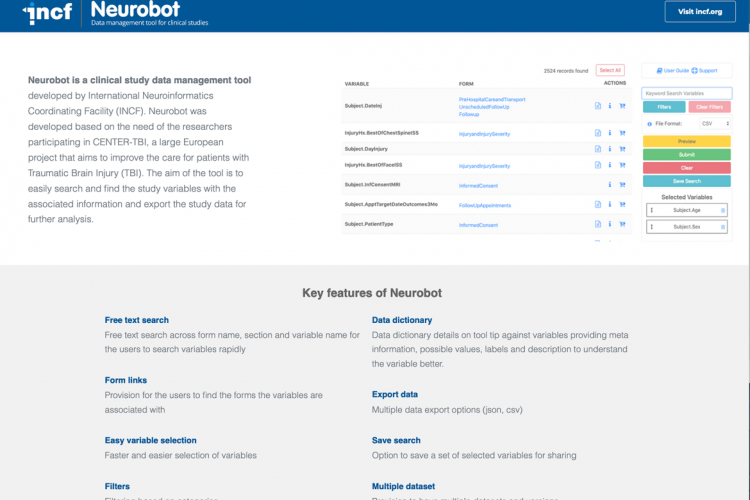

The mission of INCF is to promote the uptake of FAIR data management practices in neuroscience through the development of standards and best practices that support open, FAIR, and citable neuroscience. INCF also provides training on how standards and best practices facilitate reproducibility and enable the sharing of data and code.

INCF serves as a standards organization dedicated to open and FAIR neuroscience by vetting, endorsing, and promoting the use of community standards and best practices.

We provide educational courses and forums on FAIR data management methods & supporting tools in neuroscience through online and in-person courses and workshops.

We develop and maintain curated portfolios for standards, software tools, and infrastructure to help you implement FAIR in your neuroscience research.